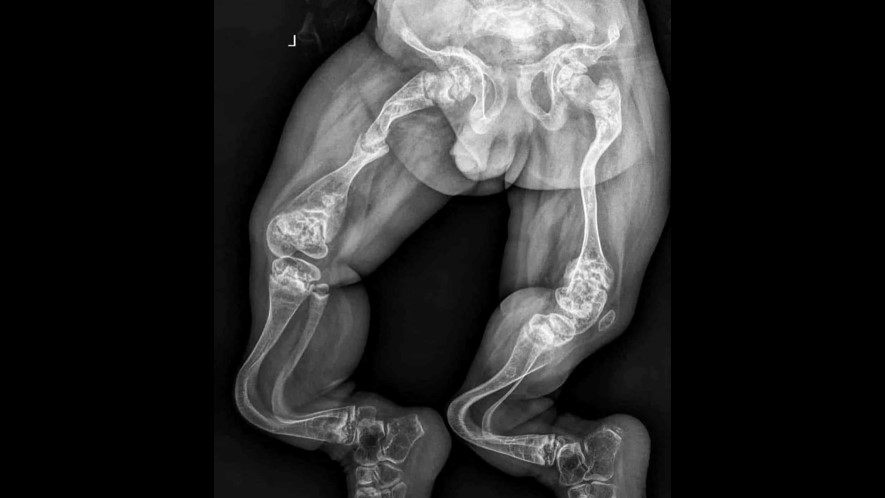

Кілька команд медичних дослідників нині тестують нові методи лікування для уповільнення або зупинки надлишкового або нестримного росту кісток, пов'язаного з прогресуючою осифікуючою фібродисплазією ПОС - рідкісним захворюванням кісток.

Донедавна не було відомо, що викликає ПОС — захворювання настільки рідкісне, що тепер від нього лікується лише 800 людей. Потім, у 2006 році, було виявлено, що воно генетично залежне — всі ті, хто страждає на цю хворобу, мають мутацію у своєму гені ALK2. Досі незрозуміло, як ген викликає надмірний ріст кісток, але дослідники підозрюють причетність сигналів, які викликають переактивацію стовбурових клітин.

Єдиним лікуванням цього стану, донедавна, була операція з видалення зайвої частини кістки, що часто призводить до прискорення росту кісток, що погіршує проблему. Через це ПОС вважається смертельною хворобою, хоча хворі можуть жити до 50 років.